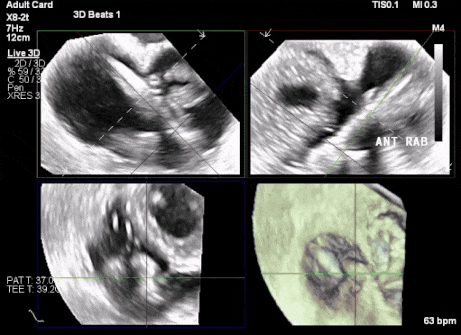

術(shù)中DSA顯示起搏器導(dǎo)線的干擾,右心室造影確定瓣環(huán)位置,操作空間小

術(shù)后超聲顯示人工瓣膜穩(wěn)定性良好,瓣葉啟閉正常